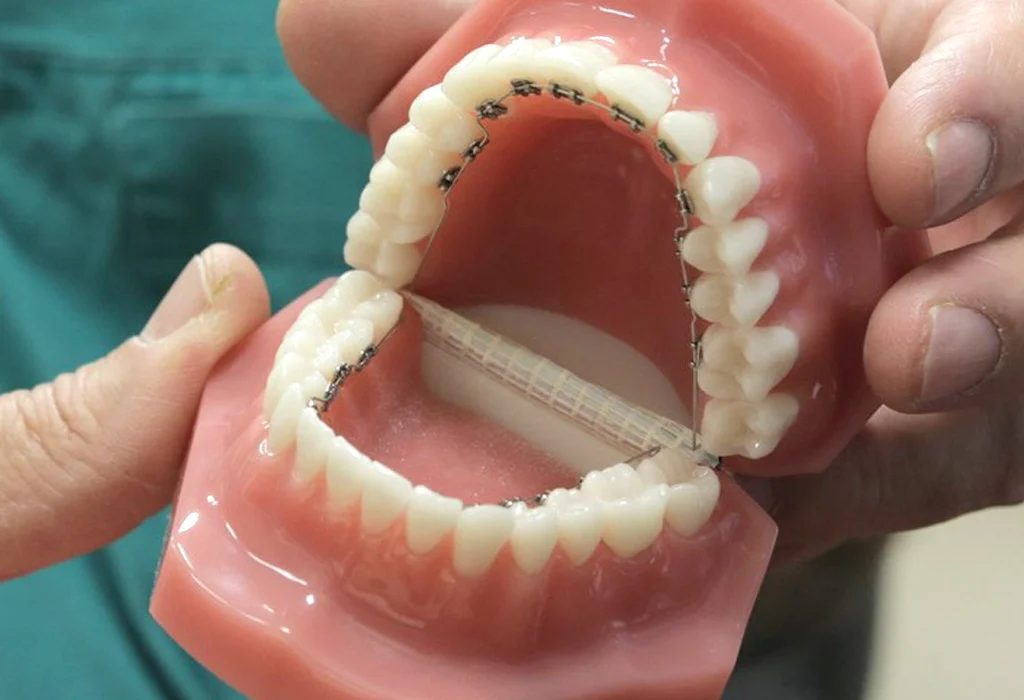

Tipi di Retainers Dentali

Esistono diversi tipi di retainers dentali, ognuno progettato per soddisfare le esigenze specifiche del paziente. I due principali tipi di retainer sono i retainers fissi e i retainers rimovibili. Vediamo le differenze principali tra i due.

1-Retainers Fissi

I retainers fissi consistono in un sottile filo di metallo che viene incollato alla superficie interna dei denti anteriori, solitamente dalla parte interna dei canini. Questo tipo di retainer è molto discreto, in quanto non è visibile dall’esterno.

Retainers Fissi

I retainers fissi sono dispositivi permanenti che vengono incollati sulla superficie interna dei denti, solitamente sui denti anteriori. Sono progettati per rimanere in posizione per un lungo periodo, senza la necessità di essere rimossi dal paziente.

Retainers Rimovibili

I retainers rimovibili sono dispositivi che possono essere facilmente tolti e messi dal paziente. Solitamente, sono realizzati in plastica trasparente o metallo e sono progettati per mantenere i denti nella loro posizione corretta durante il periodo post-trattamento ortodontico.

Come Funzionano i Retainers Rimovibili

I retainers rimovibili possono essere costituiti da mascherine trasparenti che si adattano perfettamente alla forma dei denti. In alternativa, alcuni retainers rimovibili sono dotati di un filo metallico che passa davanti ai denti. Questi dispositivi sono più facili da rimuovere e pulire rispetto ai retainers fissi.